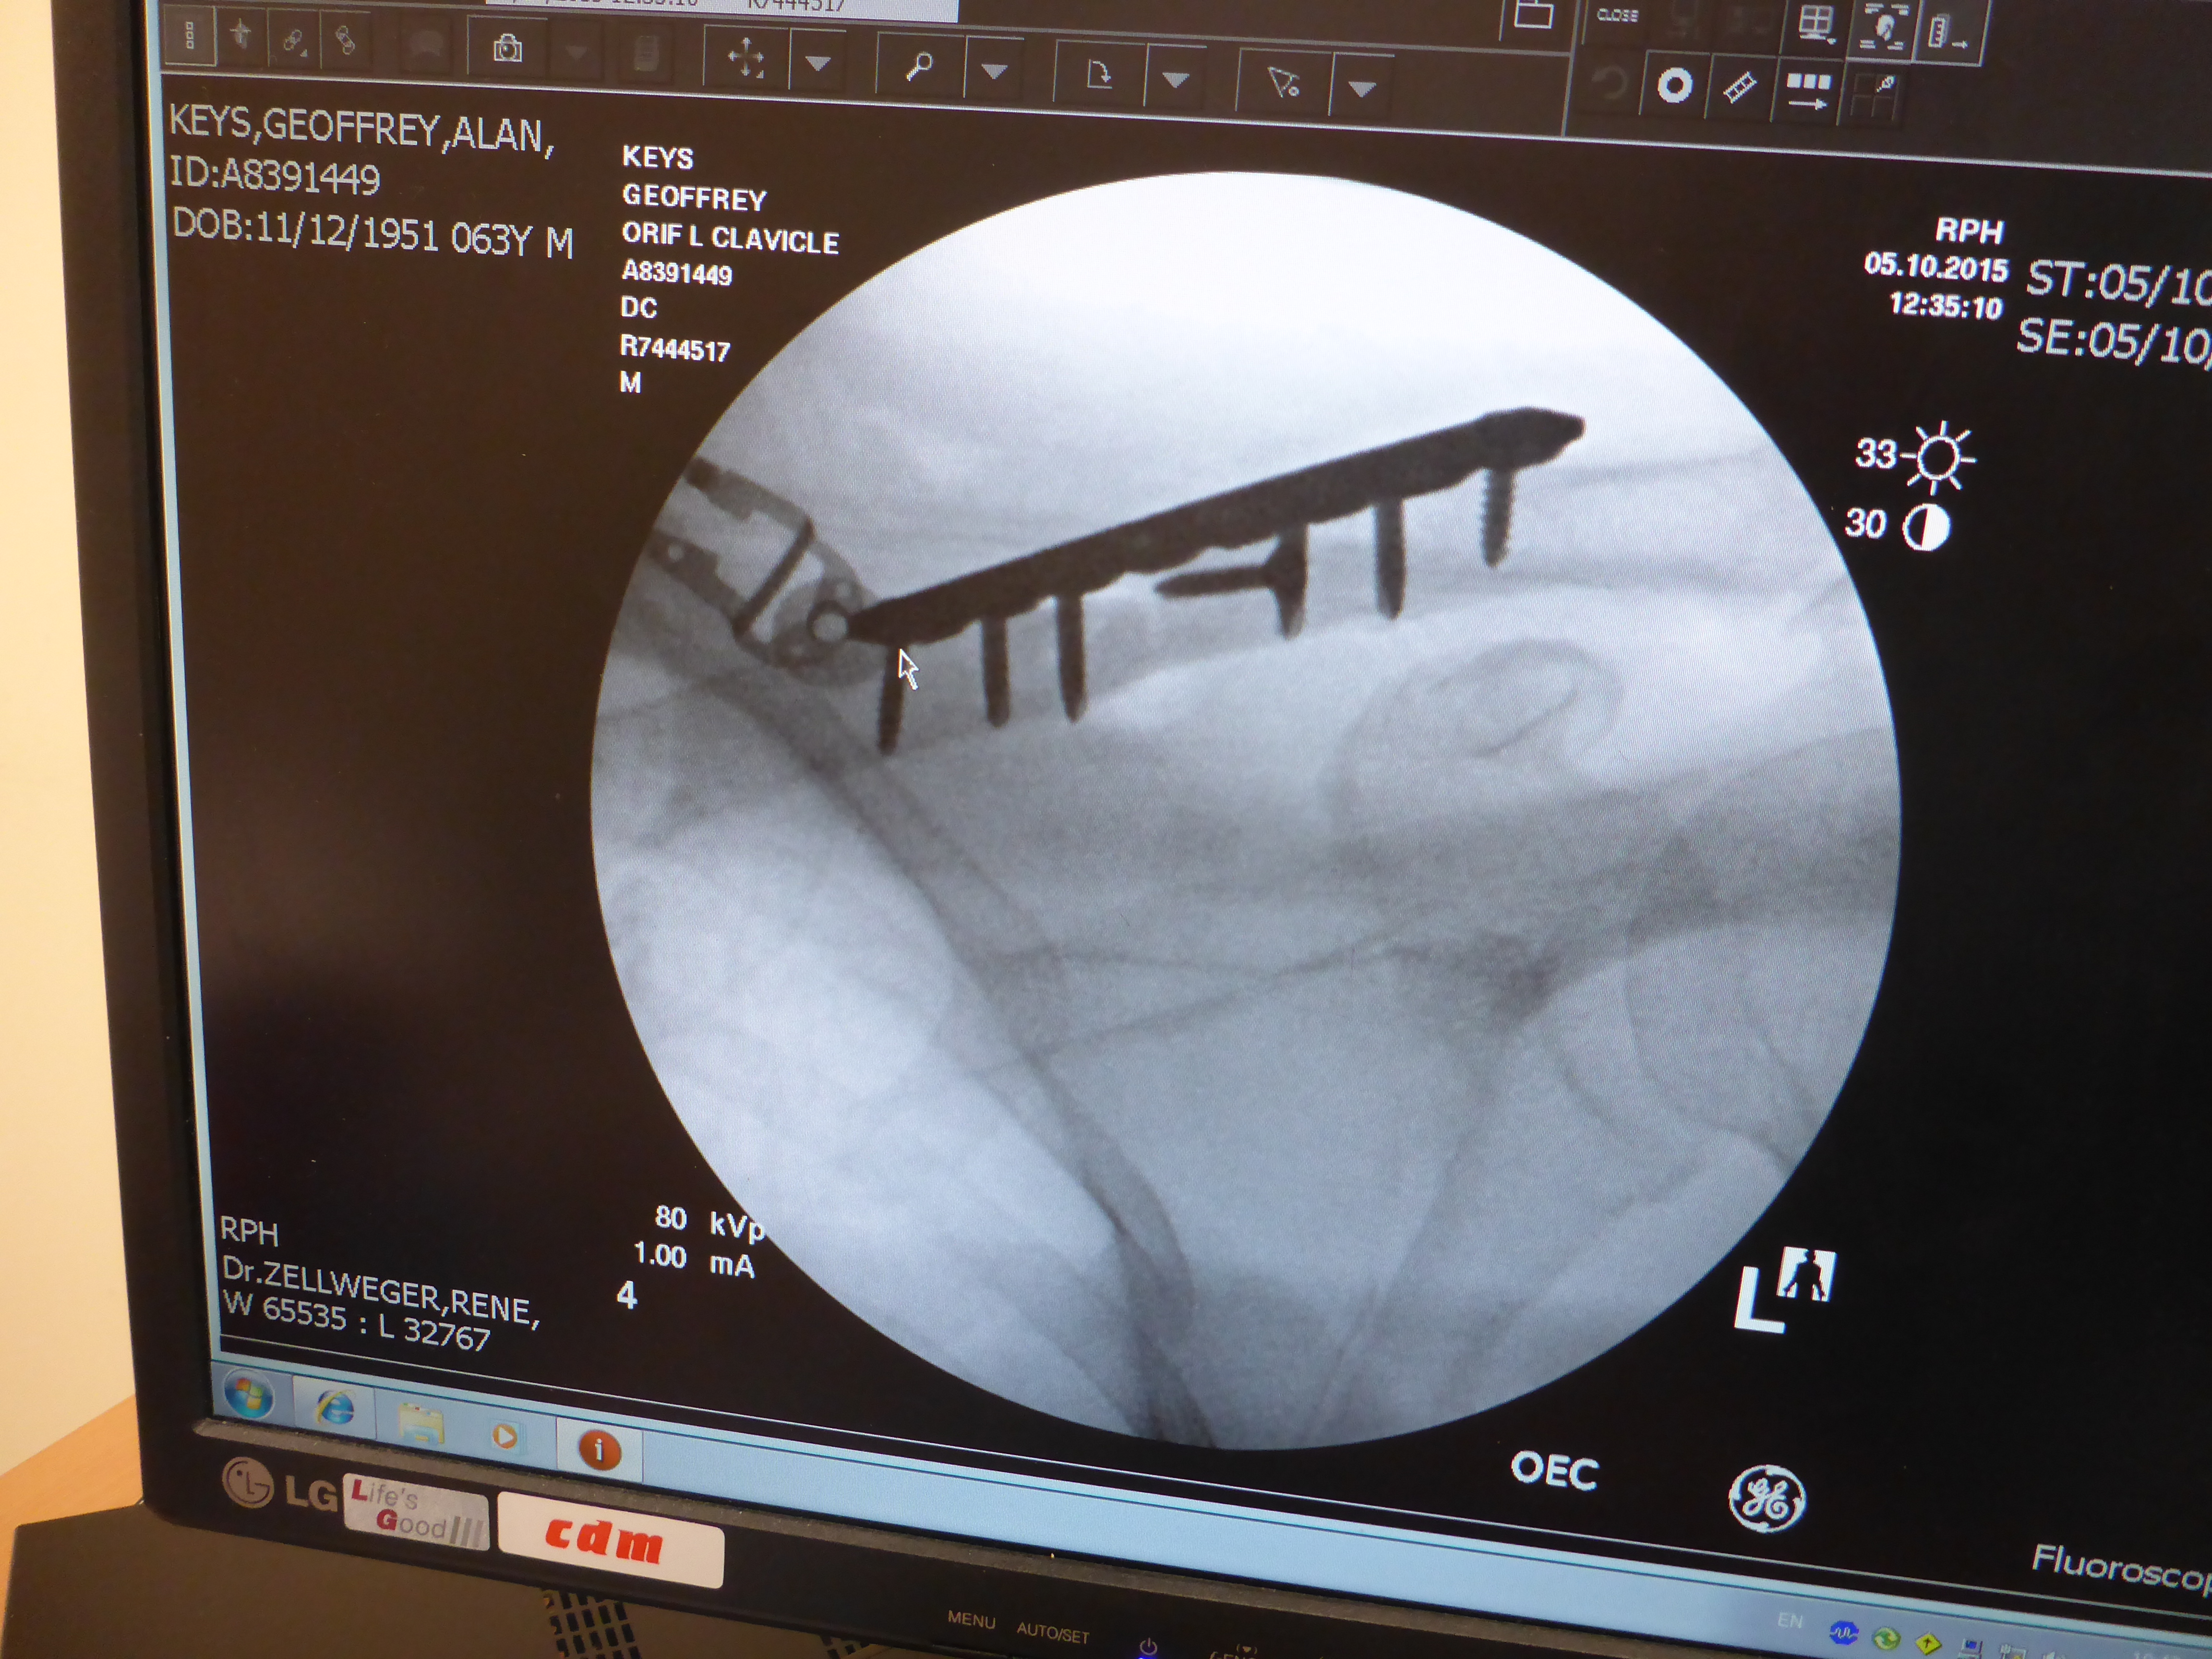

While I’d been at Tom Price I’d had two phone conversations with the orthopaedic surgeon at RPH, discussing my options. The idea was to be able to pre-plan an operation for Monday. I thought this an excellent idea and it meant that, barring some big emergency, my op was on the list before I even got there. And so it was that on Monday I was screwed and plated back together and was back in my room in time for lunch. Fantastic.